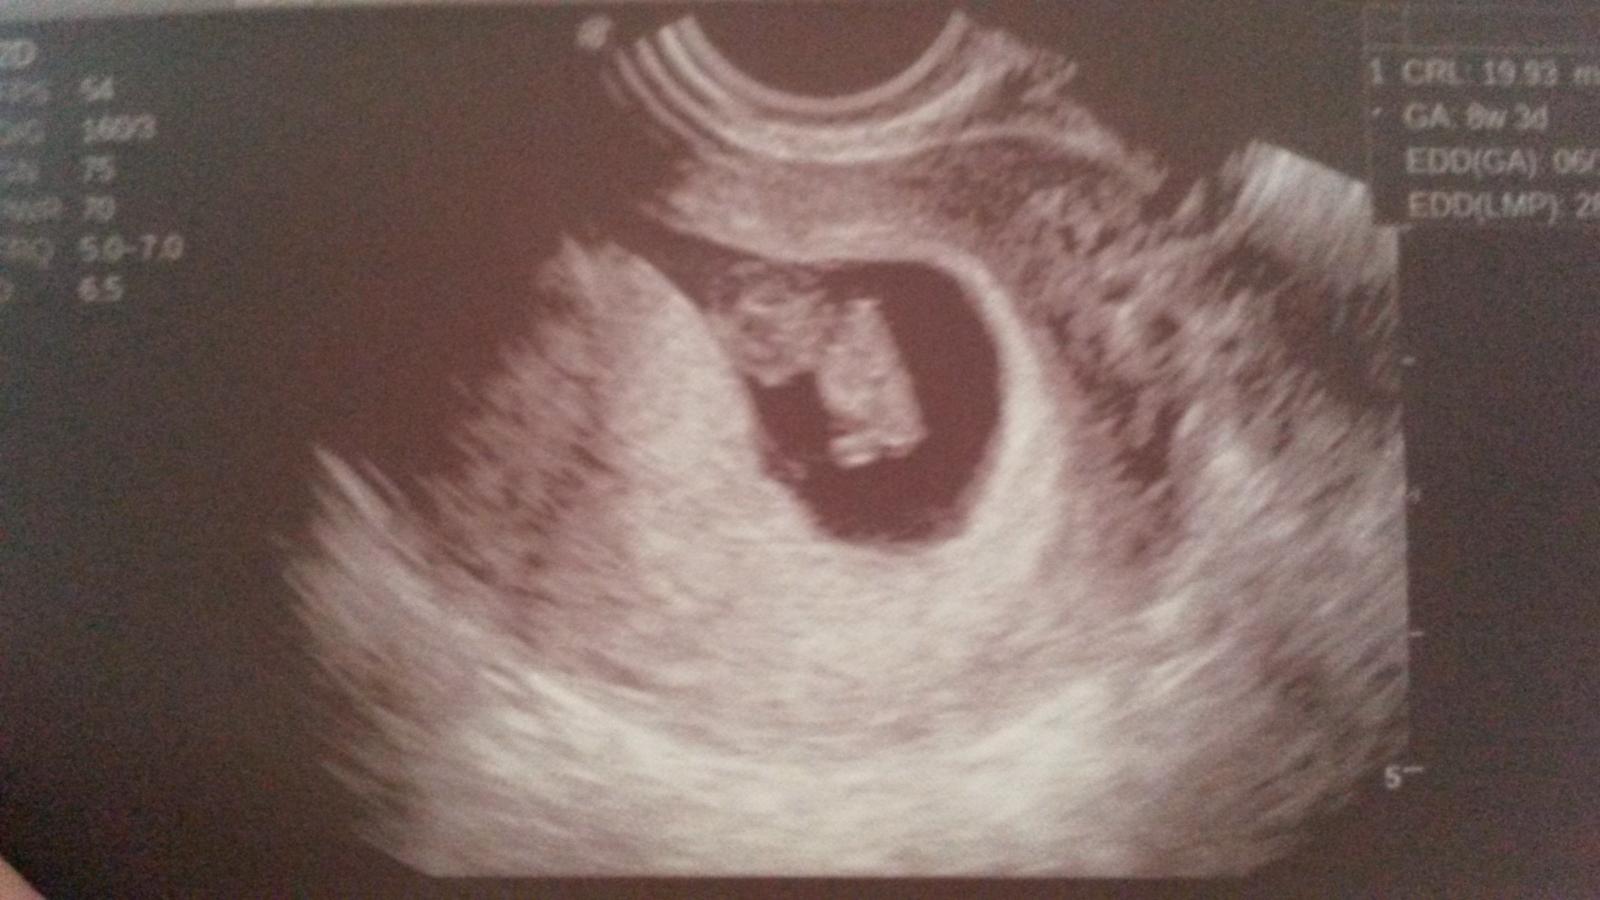

Ahojte všetky maminy aj tehuľky 🙂 🙂 chcela by som sa k Vám pridať..... zistila som, že som tehu asi pred 3 týždňami, bola som už aj u lekárky, som vo 8tt, zatiaľ všetko ok 🙂 okrem občasného špinenia, nasadila mi aj nejaké lieky na udržanie, ale nejak nestresujem, aj pri malej som chvíľu ležala, pre odlučovanie placenty 😒 . Mám už doma dve detičky ( 8,5 a 5). Ženy ja som sa tak tešila na život, konečne sú samostatný, nemusím im stále stáť za "riťou" 🙂 a zrazu bum a je to tam. Normálne som mala depku, či to zvládnem, či to chcem, či? či? a tak dookola, ale teraz sa strašne teším, nejak tie moje aktivity uhrám do menšej kôpky a bude 🙂 Aj Vám všetkým držím palčeky, nech zvládneme tie únavy, návaly tepla, zmeny nálad a ..... ako je to u mňa, hlavne hravo a zdravo a partneri - nech sa tešia a nech sú trpezlivý, však?